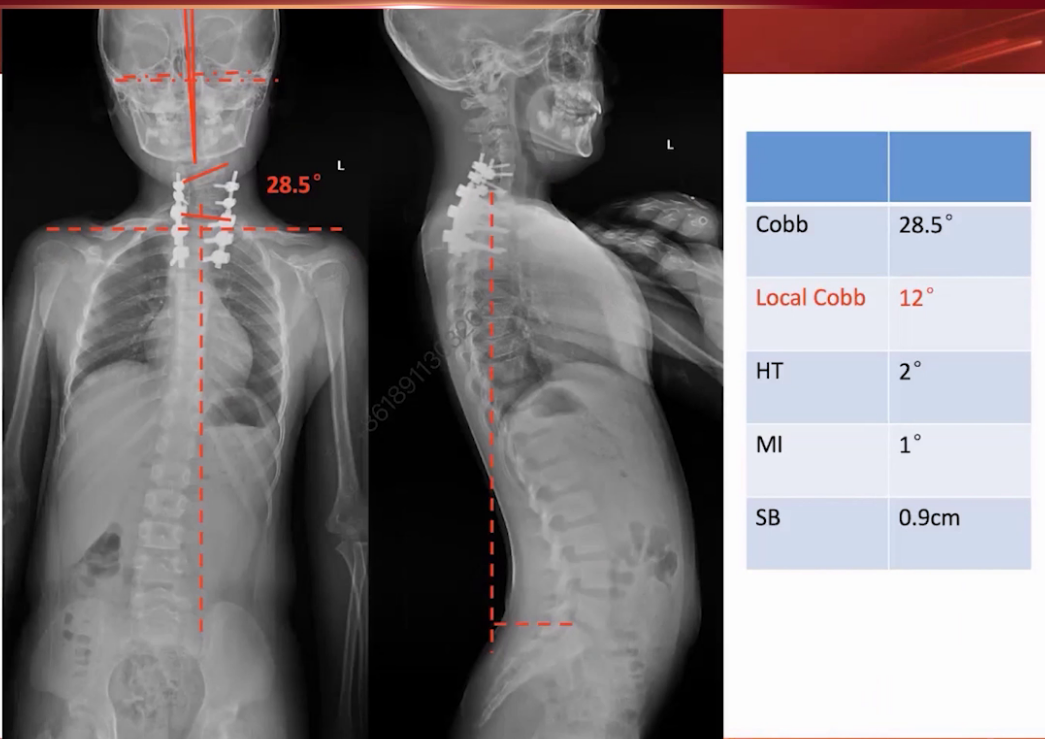

术后局部弯曲从50度改善到28.5度,头颅倾斜角和下颌倾斜角分别改善到2度和1度,肩部平衡从2.8cm改善到0.9cm,矫形效果良好,但出现矢状位平衡偏差,冠状位失衡从6mm增加到36.8mm。考虑是患儿头颅倾斜时间长,突然摆正头后身体需通过倾斜维持原有平衡姿势,后期通过代偿和步态矫正有望改善。

(2)术后一年随访发现,弯度几乎无变化,头正肩平,冠状面失衡较术后早期有所改善。